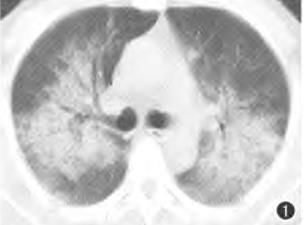

再来一个更直白的蝶翼征,几乎可以翩翩起舞了。

另外,肺水肿还可以出现肺纹理的改变:以前肺纹理少的地方,肺纹理增多;以前肺纹理相对多的地方,肺纹理更多,或者反而减少。